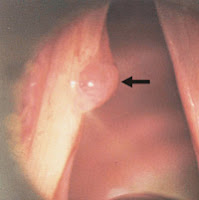

Definem-se como lesões de massa geralmente unilaterais, podendo localizar-se em diferentes regiões da prega vocal. Em 10% dos casos apresentam-se bilateralmente. São lesões mais frequentemente encontradas em adultos do sexo masculino entre 35 e 45 anos de idade.

Behlau, Madazio e Pontes (2000) citam 3 tipos diferentes de pólipos:

Pólipo gelatinoso: apresenta poucos vasos sanguíneos, é mais gelatinoso. É o tipo menos frequente.

Pólipo fibrótico: o tecido é mais vascularizado, sendo a forma progressiva do gelatinoso. É o mais comum.

Pólipo hemorrágico: é bastante vascularizado, pois apresenta grande proliferação de vasos sanguíneos.